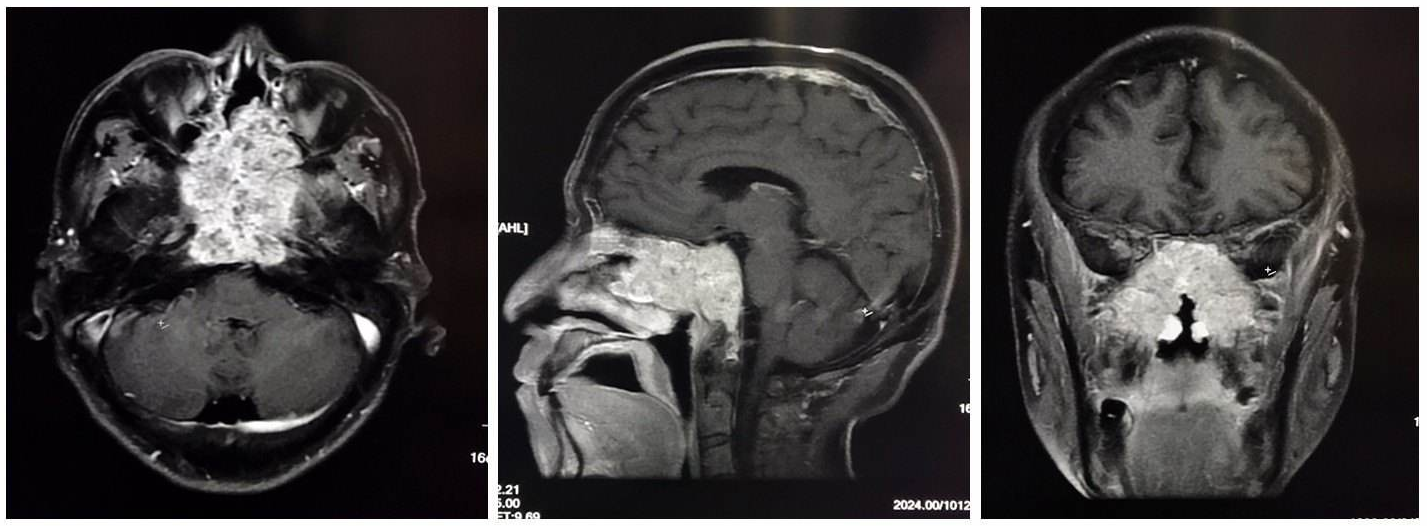

脊索瘤通常起源于中线区域,而软骨肉瘤起源于旁中线中央颅底,所以掌握周围复杂的骨性解剖结构对于成功手术治疗至关重要。 脊索瘤几乎均以斜坡为中心,斜坡分为三个部分。斜坡上段起自后床突,沿着鞍背,终止于岩尖。这一区域临近的重要神经血管结构包括动眼神经、滑车神经、三叉神经眼支和上颌支、颈内动脉海绵窦段、基底动脉上段和海绵窦。斜坡中段起自临近Dorello’s管的岩尖,止于颈静脉孔(神经部分)。这部分重要的神经血管结构包括面神经、前庭蜗神经、基底动脉下段、椎基底动脉汇合部和岩下窦。斜坡下段起自颈静脉孔(神经部分),止于枕骨大孔。这部分包括基底动脉、枕骨髁、舌下神经管,以及舌咽神经、迷走神经、副神经和舌下神经。

经鼻内镜入路是切除脊索瘤的理想入路,因为肿瘤位于硬膜外且不太可能呈纤维状;通过局部显微外科操作借助成角内镜更适于切除肿瘤。此外,采用微创开颅入路切除颅底中线肿瘤,是不太可能达到的。